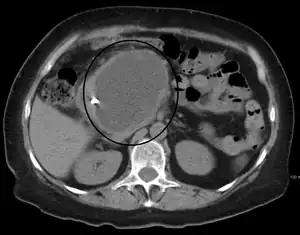

Pseudocisto pancreático

Pseudocisto pancreático é uma coleção de fluido rico em enzimas pancreáticas, sangue e tecido necrótico, envolvido por uma cápsula fibrosa e tecido de granulação, normalmente localizado no omento menor. Geralmente são uma complicação que aparece algumas semanas após uma pancreatite,[1] mas em crianças freqüentemente ocorrem após um traumatismo abdominal. Os pseudocistos pancreáticos representam aproximadamente 75% de todas as massas pancreáticas.[2]

- Tomografia computadorizada[10]: Este é o padrão ouro para avaliação inicial e para o seguimento.